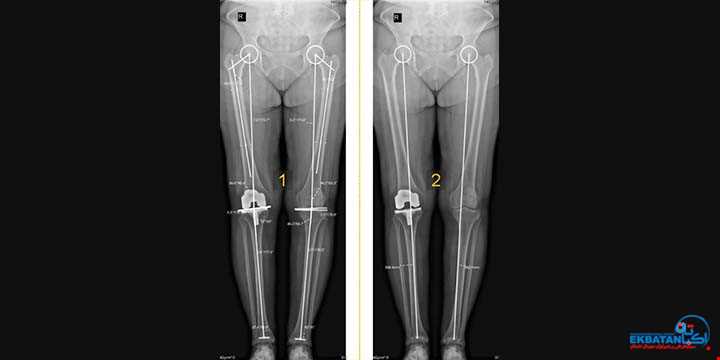

رادیوگرافی تری جوینت (سه مفصل)، استاندارد طلایی در تشخیص و درمان دقیق آرتروز زانو

آیا تا به حال احساس کرده اید که زانوهایتان فرم طبیعی خود را از دست داده اند یا به اصطلاح پرانتزی یا ضربدری شده اند؟ درد زانو تنها یک نشانه است، اما ری ...